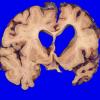

NEURODEGENERATION

Corticobasal Degeneration (CBD) (8)